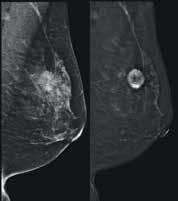

Biopsja cienkoigłowa pod kontrolą USG

Podejrzane objawy BIA-ALCL > 1 rok od implantacji USG piersi

Powiększenie węzłów chłonnych pachy

Rezonans magnetyczny